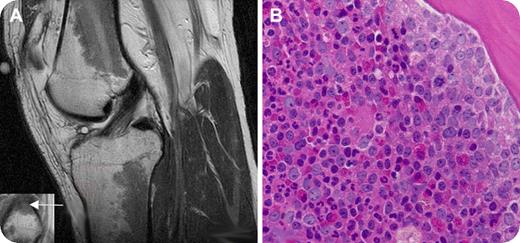

A 27-year-old man presented with a complaint of several months of progressive left knee pain with ambulation. An MRI scan of the left knee revealed extensive intermediate-low-signal intensity within the bone marrow in the diametaphyseal regions of the distal femur and proximal tibia (panel A, sagittal T2-weighted image of knee joint) and the epiphysis of the proximal fibula (panel A inset, coronal T1-weighted detail of fibular epiphysis; the arrow shows the bone marrow abnormality). The patient denied a history of knee trauma and was otherwise healthy. He had no knee abnormality on examination. There was no enlargement of lymph nodes, liver, or spleen.

Laboratory tests showed a white blood cell count of 25.3 × 109/L with 55% neutrophils, 8% bands, 5% myelocytes, 6% metamyelocytes, 21% lymphocytes, 4% monocytes, and 1% basophils; hematocrit of 43.7%; and platelet count of 203 × 109/L. A bone marrow aspirate and biopsy from the left posterior-superior iliac crest revealed hypercellularity with granulocytic predominance (panel B). Karyotypic analysis revealed a Philadelphia chromosome (t (9;22)). The patient was diagnosed with chronic myelogenous leukemia (CML) and therapy with imatinib mesylate was initiated.

The abnormalities on the MRI scan, when viewed in the absence of known hematologic abnormalities, were initially attributed to red marrow reconversion, which may be secondary to athletic activity. However, similar findings can indeed be seen in myeloproliferative disorders and marrow replacement disorders. Clinicians should be aware of unusual presentations of hematologic disorders in seemingly healthy patients with abnormal bone marrow signal on MRI scans.